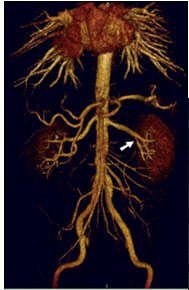

![]() |

| Coronal 3D volume rendered from CEMRA in a 54-year-old man with uncontrolled hypertension. By acquiring images over a large field-of-view on a high-resolution matrix, the arteries of the entire abdomen, pelvis, and lower thorax are visualized in detail. |